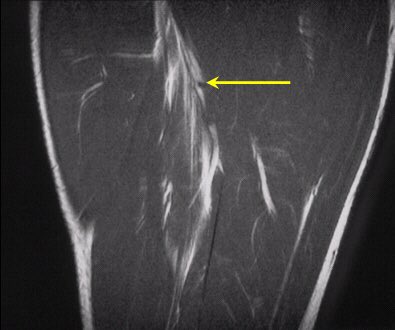

النوع الثاني: تمزق في العضلة الخلفية للفخذ بعد إطالة عالية ومفاجئة للعضلة.

ويحدث غالباً في منطقة الوتر مع التقاءه بعظمة الحوض من الأعلى.

- الوتر هي المنطقة البيضاء بالصورة.

ويكثر في الرياضات التي تتطلب حركات عالية مثل: ( رياضة الجمباز ، الهوكي ، رقص الباليه ، وأيضاً كرة القدم ).